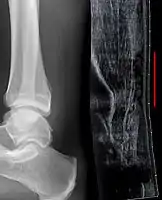

Radiography can also be used to indirectly identify Achilles tears. Radiography uses X-rays to analyse the point of injury. This is not very effective at identifying injuries to soft tissue. X-rays are created when high energy electrons hit a metal source. X-ray images are acquired by utilising the different attenuation characteristics of dense (e.g. calcium in bone) and less dense (e.g. muscle) tissues when these rays pass through tissue and are captured on film. X-rays are generally exposed to optimise visualisation of dense objects such as bone while soft tissue remains relatively undifferentiated in the background. Radiography has little role in assessment of Achilles' tendon injury and is more useful for ruling out other injuries such as calcaneal fractures.[13]

Achilles tendon avulsion seen on plain X-ray

Achilles tendon rupture seen on ultrasound. Note discontinuity over several centimeters (red line). No fracture or avulsion (radiograph).